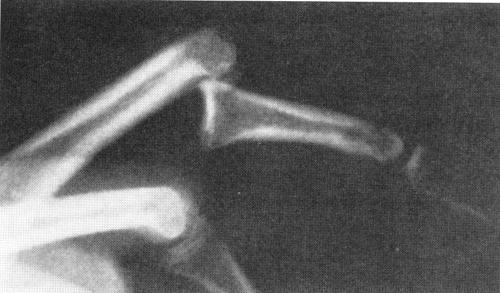

swan neck deformity

Primary lesion is lax volar plate that allows hyperextension of PIP

Secondary lesion is imbalance of forces on the PIP joint: